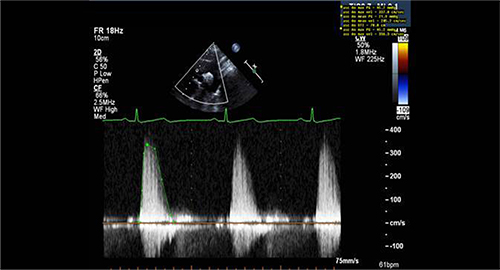

Figure 1: Sample of Doppler image and measurements obtained from apical window in a patient with aortic stenosis.